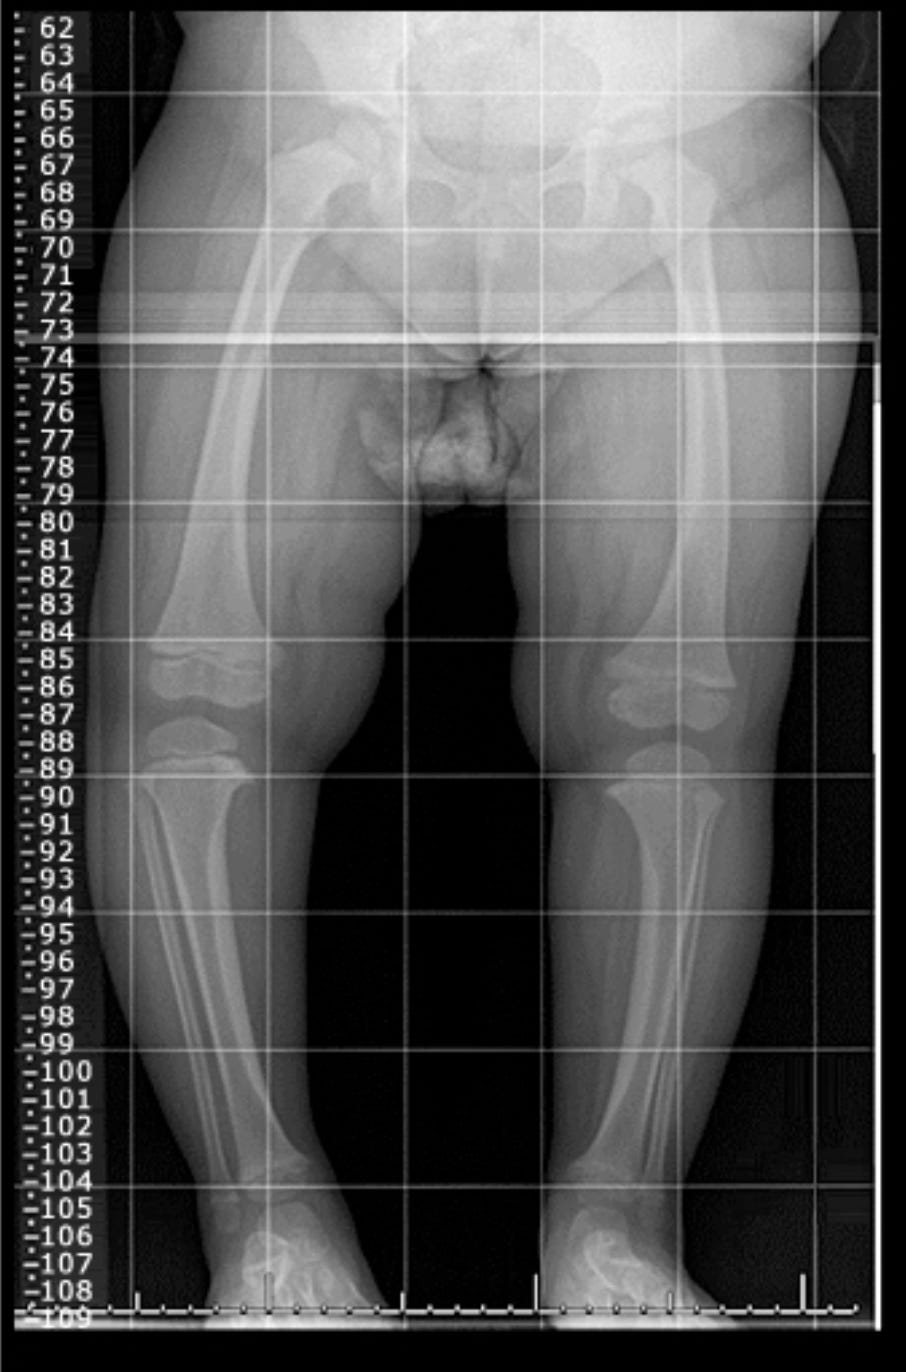

Рентгенологические признаки:

Снижение плотности костной ткани

Расширение и "чашеобразная" деформация ростковых зон

Расширенные метафизы

Псевдопереломы (зоны Лоозера)

Деформации длинных костей

Переднезадние рентгенограммы обеих нижних конечностей в положении стоя помогают отличить физиологическую О-образную деформацию от патологической У этого пациента с Х-сцепленным гипофосфатемическим рахитом (XLH) отмечаются множественные расширенные зоны роста. В метафизах видна остеопения, сам метафиз расширен. Искривление обычно более диффузное по всей кости, а не локализуется в области проксимальной большеберцовой кости.

Техника рентгенографии:

Оптимальная техника:

Телерентгенограмма: изображение всей нижней конечности от тазобедренных суставов до стоп обеих нижних конечностей

Положение пациента: стоя (если возможно)

Положение стоп: в комфортном положении, НЕ сведенные вместе

Критически важно: надколенники должны быть направлены прямо вперед, независимо от того, стоит ребенок или нет

Важность правильного позиционирования: позволяет точно оценить степень варуса и проводить серийные сравнения при необходимости